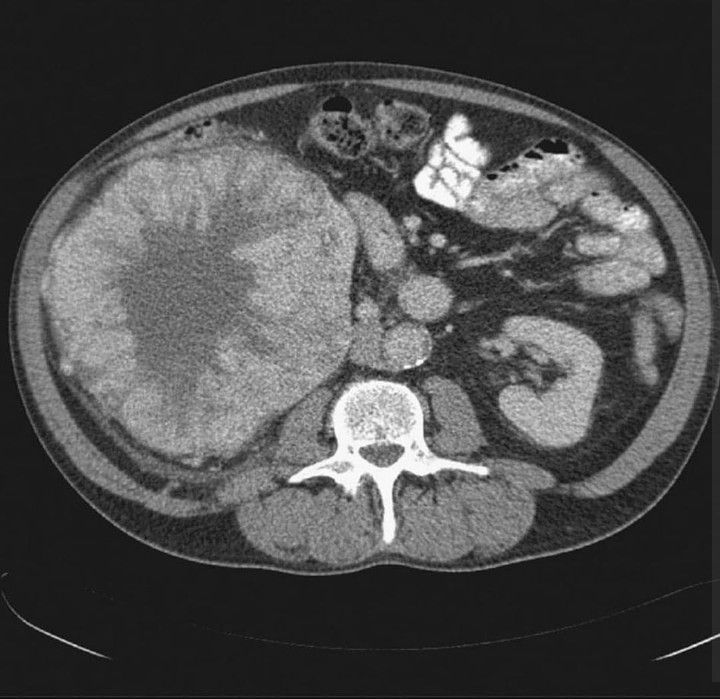

61-year old male patient presented with lower back/right flank pain. CT showed large right renal mass and radical nephrectomy was performed. PH confirmed typical features of oncocytoma without evidence of malignacy. Renal oncocytomas are relatively benign renal tumors. Very often they are pre-operatively difficult to distinguish from renal cell carcinomas. Usually they are asymptomatic, but flank pain,hematuria or hypertension may be present. Enchacement on CT is usually heterogeneous and central stellate non-enhancing scar is seen in ~33% cases. (case credits: S. Ahmad, R. Manecksha)